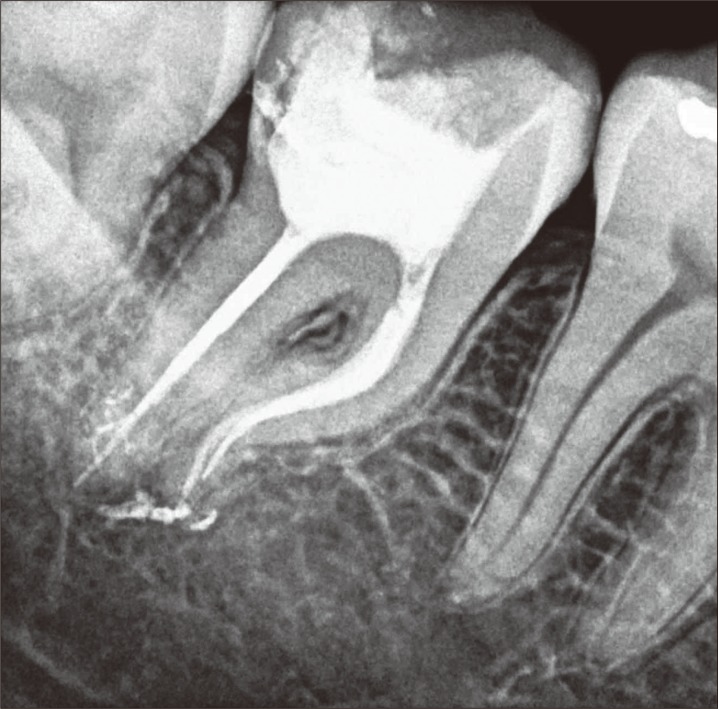

The patient, a 22-year old man, complaining of moderate pain in tooth #47 upon chewing, was referred to the Dental Clinic of the Federal University of Amazonas, Brazil. The patient did not have any systemic diseases and were not under any type of medication or drugs. Intraoral examination revealed the presence of a temporary restoration. The tooth was tested for pulp sensibility with Endo Frost spray (Roeko GmbH & Co., Langenau, Germany) and responded positively to the cold test, and negatively to the mobility test. The periapical radiographic examination revealed that the temporary restoration was extremely deep, since the tooth had already been submitted to pulpotomy procedure. Moreover, an accentuated dilaceration in the mesial root, a developmental anomaly characterized by an abrupt change in the axial inclination of the root, was observed. Also, no periapical lesions were observed (Figure 1).

The tooth was diagnosed as asymptomatic irreversible pulpitis and endodontic treatment was instituted. After local anesthesia (Xylestesin 2%, Cristália Produtos Químicos Farmacêuticos Ltda., Itapira, SP, Brazil) and rubber dam isolation (Hygienic, Coltene/Whaledent AG, Alstatten, Switzerland) of the operative area, the temporary restoration was removed and pulp chamber access procedure using spherical burs No. 1013 (KG Sorensen, São Paulo, SP, Brazil) and tapered flame shaped burs No. 2200 (KG Sorensen) was performed. Next, the root canals orifices were located with the aid of a straight exploratory probe. The glide path was performed using #10 K-files (Dentsply Maillefer, Ballaigues, Switzerland) and Pathfile #13, #16 and #19 (Dentsply Maillefer) up the working length of 18 mm.